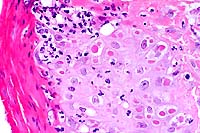

- Case 24-4. Small intestine. Thickened, blunted villi

are expanded by abundant lymphocytes, macrophages, and fewer

eosinophils. The hypertrophic, vacuolated endothelium of a small

arteriole is infiltrated by lymphocytes and neutrophils.